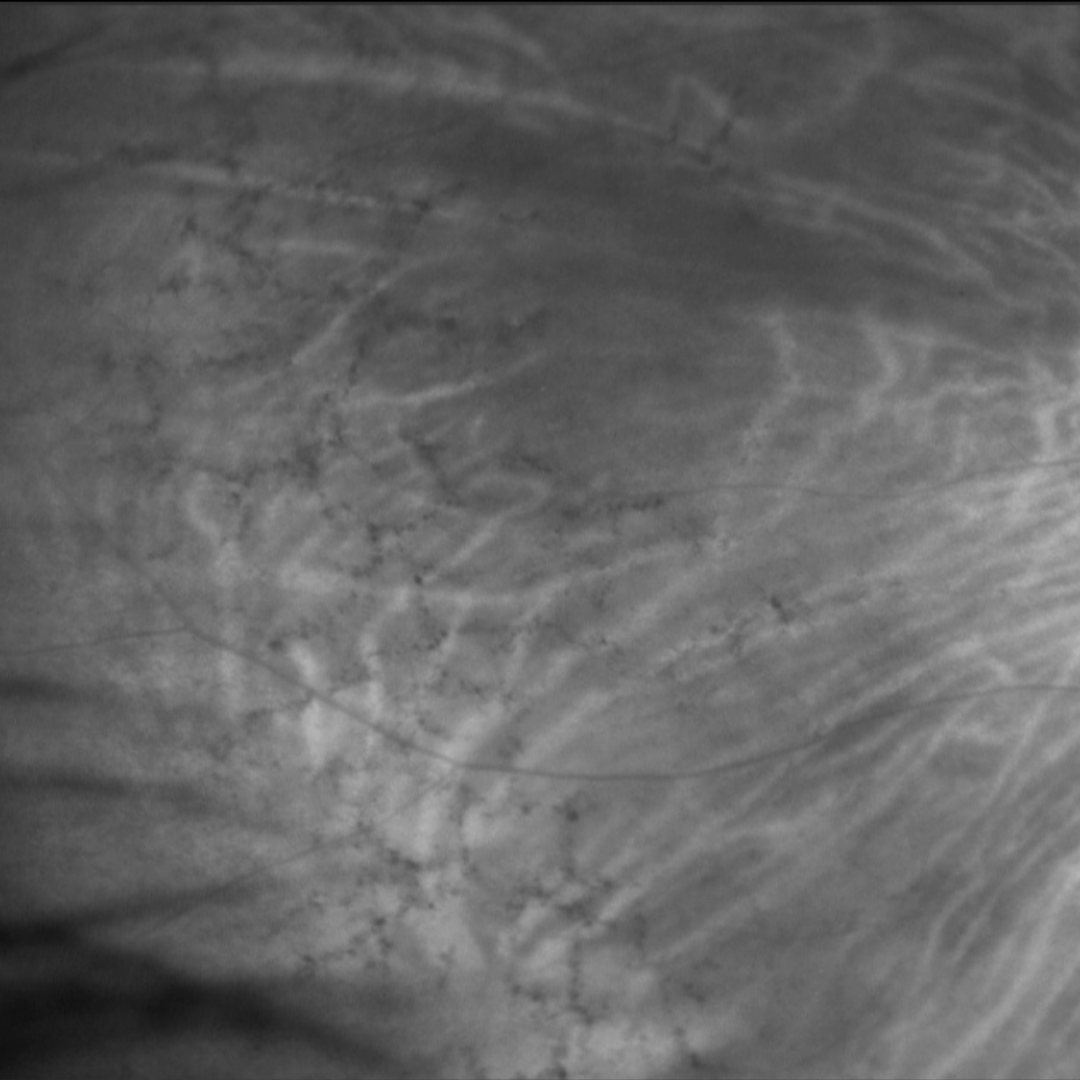

Peripheral reticular pigmentary degeneration (also known as senile reticular pigmentary degeneration) is characterised by reticular or net-like pigmentary changes that form geometric patterns in the peripheral retina, often accompanied by peripheral drusen. These may appear similar to the bone-spicules in retinitis pigmentosa. However, unlike retinitis pigmentosa, it does not impact visual function or the visual field.

Fundus changes are typically bilateral and superonasal in location, however, it can extend to the temporal retina in some cases. The incidence of PRPD increases with age.

A 72 year old Caucasian female with best corrected visual acuities of 6/7.5 (20/25) in each eye.